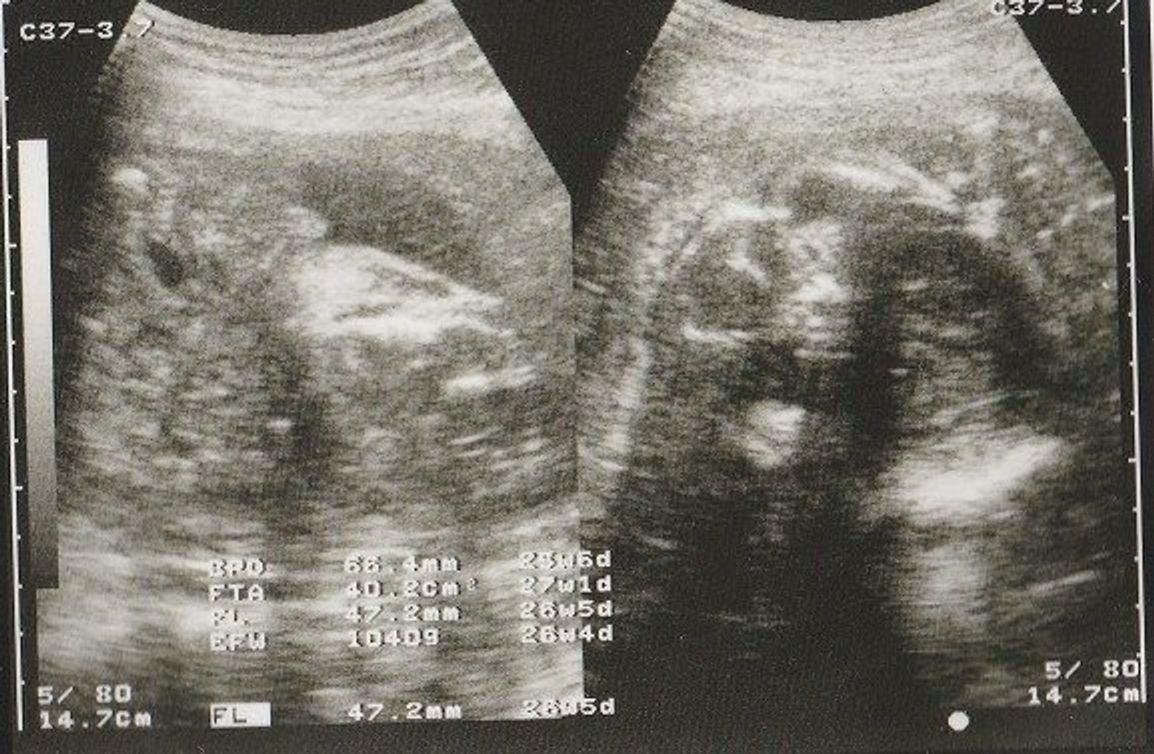

エコー写真の用語:頭部(BPD) BPD:児童大横経(頭の横幅の長さ) GA:エコー測定値から算出した妊娠週数 SD:標準偏差(統計上のばらつき) BPD 599mm GA 24w3d14SD この写真では、頭の横幅の長さが599mm、それは妊娠24週3日目の標準と同じ位で、標準偏差妊娠 性別詳しいかたお願いします 5ヶ月エコーなんですがおちんちんとたまにしかみえないから男の子と数名に言われたんですが三本線あるから女の子ぢゃない?て聞いたらお股から写したやつなら三本線てゆーけ 質問No

今日でW!6ヶ月です!! 妊娠生活も折り返し地点かと思うと、感慨深いです。 そして、今日は月1の診察日でした。 胎動を感じてからは初めての検診だから、 今までみたいに「生きてるかしら?元気かしら?」って不安がないのは 大きな変化だね。女の子エコー写真股 最高 3dエコー 女の子女の子 エコーって、普遍てきな話題かも・・・って、女の子 エコーについては、思ってりしますね! エコー写真。 妊娠七ヶ月 (26週)見て股を閉じていました。 閉じていた少しの隙間から突起物みたいなのが見え 骨盤の男女差や違いを画像を用いて解説します 私たち人間の身体機能の核心である骨盤。 その骨盤は男性と女性で形が違うのをご存知でしょうか。 医療従事者でなければあまり意識することはないかもしれませんが、よくよく考えてみると骨盤に収まっ